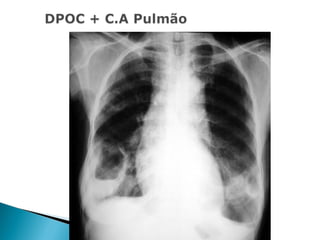

   Congestão:

. Dilatação dos vasos.

. Redistribuição do fluxo sanguíneo para as

zonas superiores.

. Edema intersticial e alveolar.